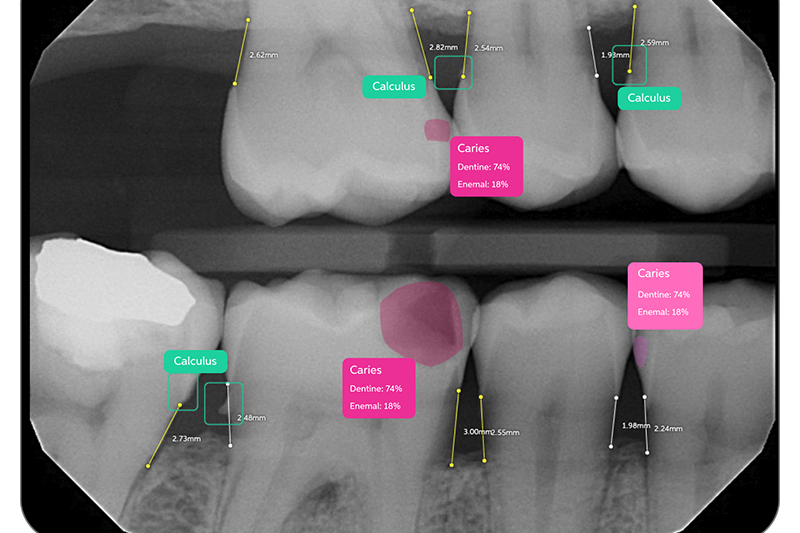

Pearl AI

Pearl AI is cutting edge technology. It’s a powerful tool that uncovers hard-to-see disease including early decay and bone loss with a high level of accuracy